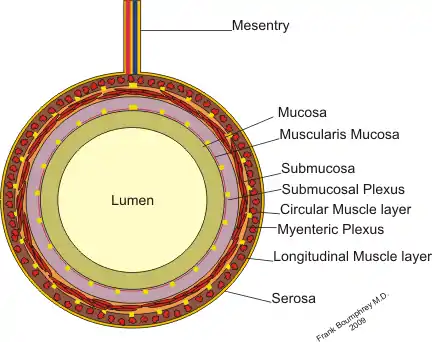

The GI tract is essentially a hollow tube connecting the mouth to the anus. The GI tract has a similar layout through out its length:

- An inner mucosal layer with an epithelial lining

- A submucosal layer

- A thin layer of muscle , the Muscularis Mucosa is at the junction of the mucosal and sub mucosal layers, outside this are the nerves of the mucosal plexus

- A muscular layer with an inner circular muscle layer and an outer longitudinal layer

- Between the muscles are the nerves of the myenteric plexus

- A serosal layer which is continuous with the mesentry

This is illustrated graphically here: